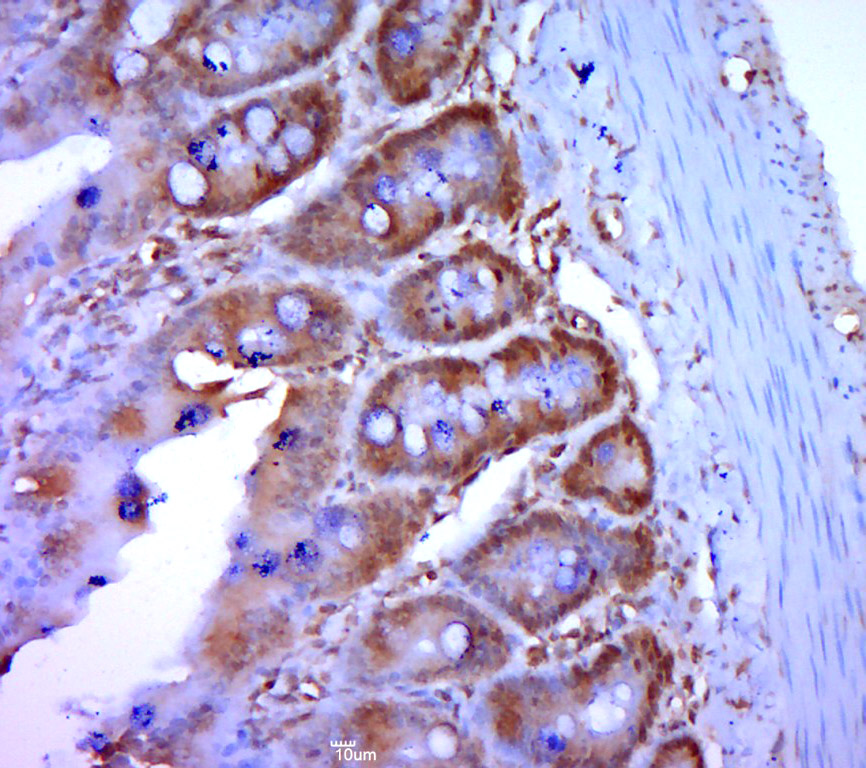

| 英文名称 | Eps8L3 Rabbit pAb |

| 中文名称 | EPS8相关蛋白3抗体 |

| 产品应用 | IHC-P=1:100-500, IHC-F=1:100-500, IF=1:100-500 Not yet tested in other applications. |

| 交叉反应 | Rat (Human, Mouse, Dog, Pig, Cow, Sheep) |

| 亚细胞定位 | Cytoplasmic |

| 组织特异性 | Highly expressed in brain; expressed in embryonic floor plate, roof plate and hindbrain segments. |

| 功能 | EPS8 like protein 3 is related to epidermal growth factor receptor pathway substrate 8 (EPS8), a substrate for the epidermal growth factor receptor. The function of this protein is unknown. Alternatively spliced transcript variants encoding different isoforms exist. |

| {IHC-P} | {1:100-500} |